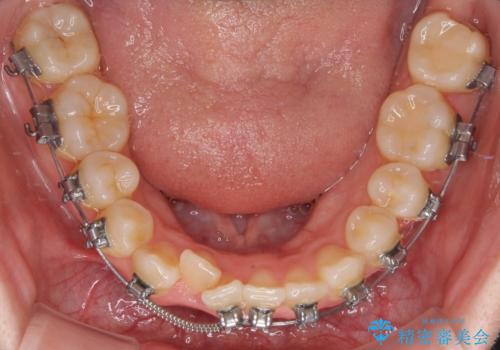

- 矯正装置

- メタルブラケット

また、抜歯して確保したスペースが不足してしまうのを防ぐため、補助装置を併用しています。